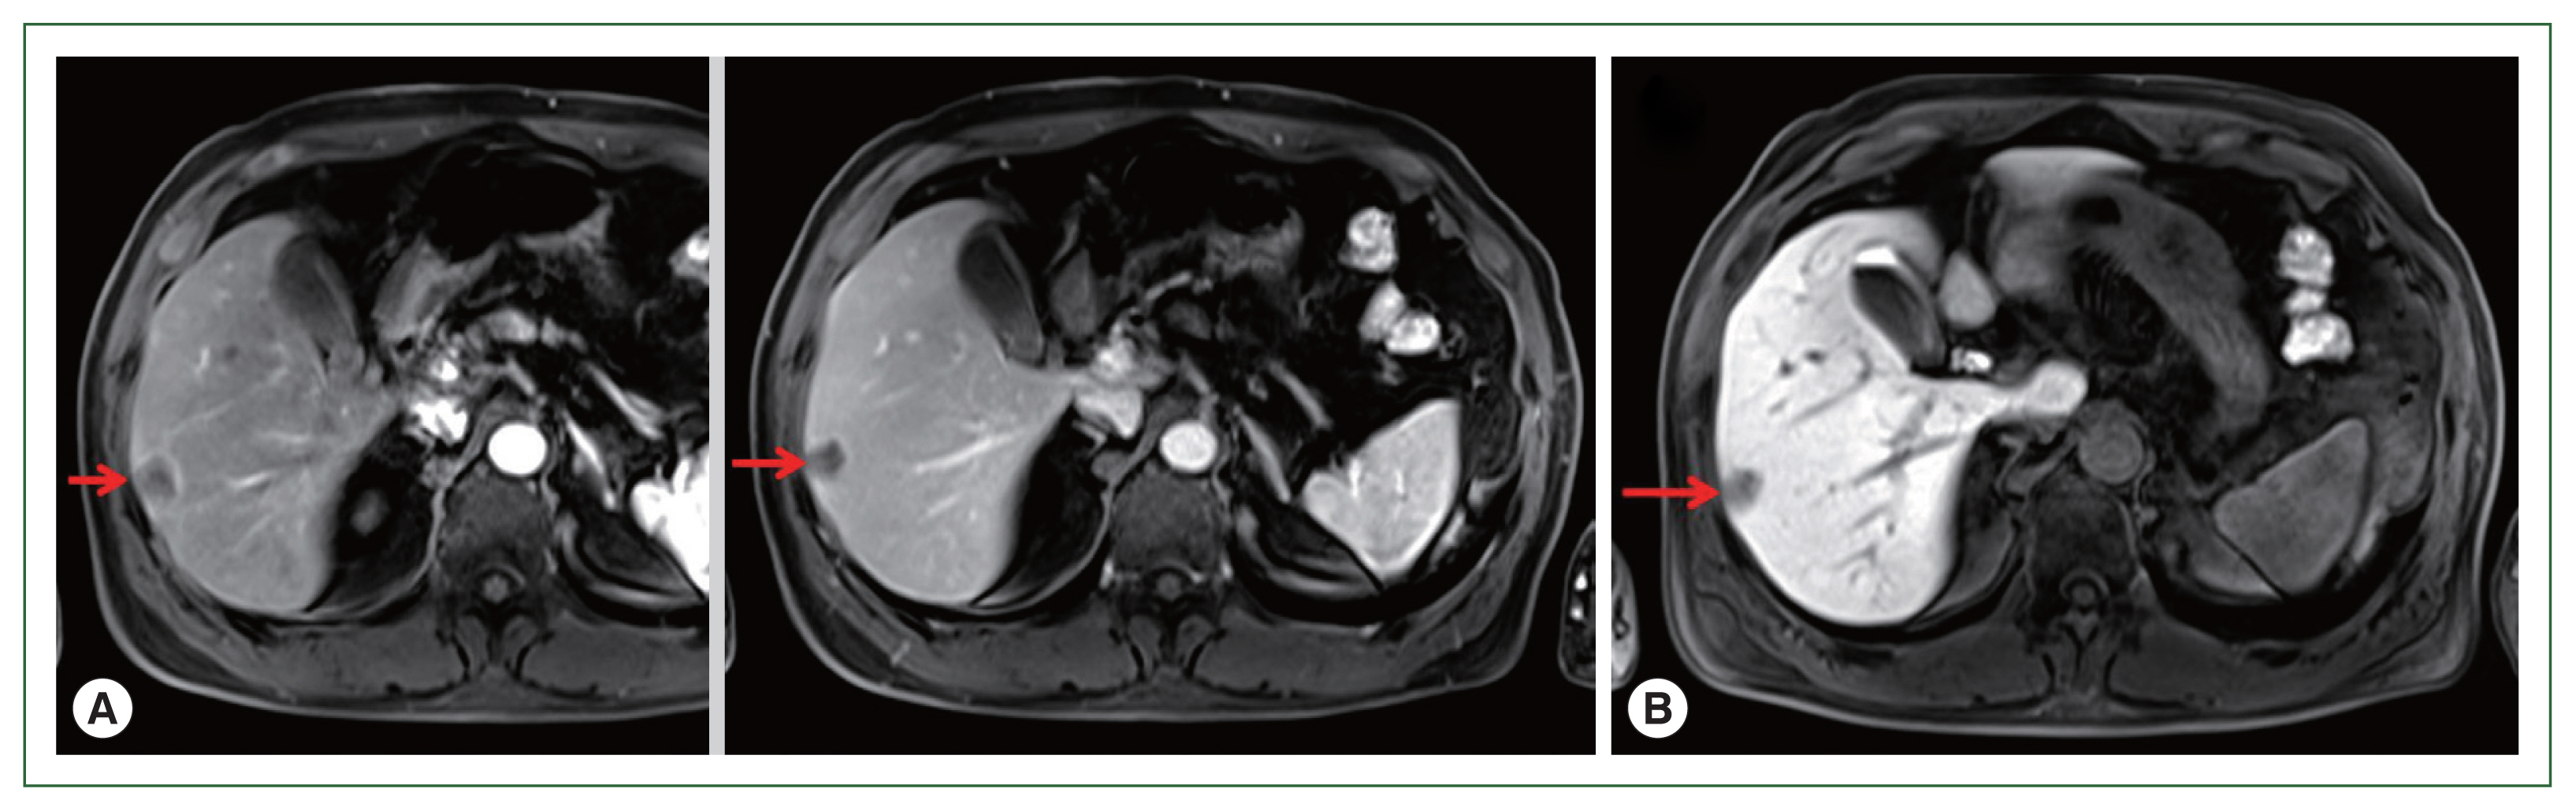

A 71-year-old male patient was admitted to Kyoto Prefectural University of Medicine Hospital with a liver tumor impression. He had a previous history of hypertension, gout, and prostatomegaly. He underwent appendectomy at 30 years of age. He had a family history of lung cancer, which affected his mother. Abdominal ultrasonography performed in health check-up revealed a low-density area of 20 mm in diameter in segment 6 of the liver. He was referred to our hospital for a more detailed lesion examination after 1 month. Difficulties were associated in reaching a definitive diagnosis although computed tomography (CT)-ethoxybenzyl-diethylenetriamine pentaacetic acid-enhanced magnetic resonance imaging (EOB-MRI) images were investigated (Figs. 1, 2). Therefore, a liver biopsy was performed and tissue sections were examined. Preoperative diagnosis includes a liver tumor (S6), and a differential diagnosis from hepatocellular carcinoma, metastatic liver cell carcinoma, cholangiocarcinoma in the liver, and an inflammatory pseudotumor was required. Borderline-limited necrotizing granuloma comprising coagulation necrosis containing eosinophilic ghost cells and liquefactive necrosis with a desquamated cytoplasm was revealed in a pathological examination of a tissue section from a surgical sample obtained under laparoscopy. Necrotizing granuloma of the S6 lesion in the center of the tissue section was partially resected, revealing avascular necrosis in the cavity, and contained a necrotic larval nematode with a thick pellicle and amorphous content, indicating an anisakis infection (Figs. 3, 4). Necrotizing eosinophilic granulomatous connective tissues surrounding the larval nematode were visualized with hematoxylin and eosin staining, but were not clarified by Victorian-blue or elastica staining (Figs. 5, 6). DNA samples were extracted from parasite-positive and -negative regions in paraffin-embedded sections using the DEXPAT reagent (TaKaRa, Shiga, Japan) and the QIAmp DNA Mini Kit (Qiagen GmbH, Hilden, Germany) to molecularly identify the larvae in the nematode-positive lesion. A nuclear DNA region of internal transcribed spacer (ITS)1, 5.8S rRNA and ITS2, and a mitochondrial DNA region of COX2 are used to identify Anisakis larvae. The COX2 region was amplified by polymerase chain reaction (PCR) and sequenced in the present case. The primers used for COX2 were 5′-TCAGGATTTTGGTTTGATGTTT-3′ and 5′-ATTCTCCATAAAACCTATACAC-3′ [10]. A PCR reaction was performed under the following conditions: samples were denatured at 95°C for 3 min and then subjected to 40 cycles of 94°C for 30 sec, 48°C for 40 sec, and 72°C for 50 sec, with final extension at 72°C for 7 min on a thermocycler (GeneAmp PCR System 9700, Applied Bio-systems, Foster City, CA, USA). The PCR product (682 bp) was purified with a QIAquick PCR Purification Kit (Qiagen GmbH) and sequenced. Clustal X2 [11] aligned sequences and BioEdit 7.0.5.3 manually edited computed sequences [12]. All gaps were eliminated and COX2 sequences were used for the phylogenetic analysis. A maximum likelihood (ML) analysis was performed with MEGA 6.0.6 [13]. The substitution model and optional parameter sets used were assessed with MEGA 6.0.6, and the most suitable sets were selected following the Akaike information criterion. The same datasets were used to construct 1,000 ML trees to calculate the bootstrap values. the final dataset contained 468 positions. Molecular and phylogenetic analysis of COX2 (468 bp, partial sequence) sequences revealed Anisakis larvae belonging to A. pegreffii (Fig. 6).